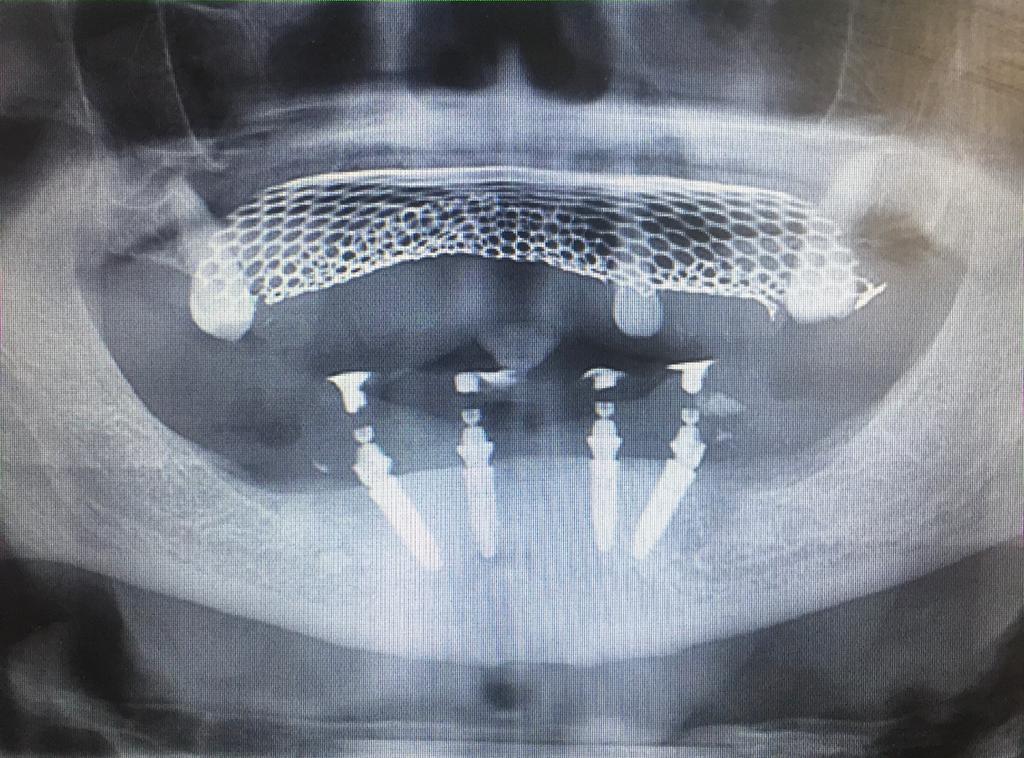

EXPANSION DE CRÊTE

ALL ON SIX

ALL ON FOUR